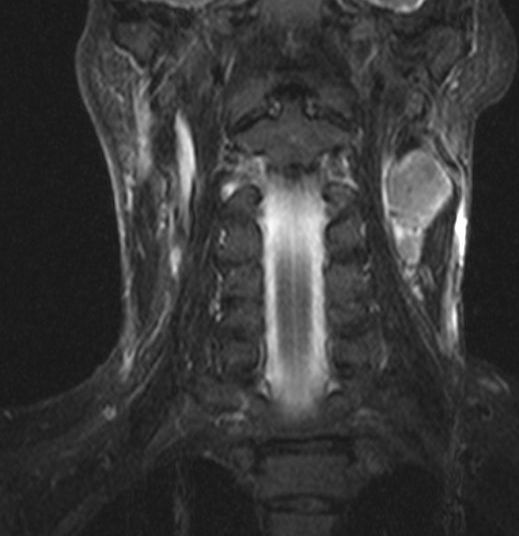

51-jähriger Mann mit Tonsillenkarzinom pT2 pN2b Mo. Tonsillentumor asymptomatisch.

Das große Lymphknotenpaket am Unterkieferwinkel war aufgefallen. |